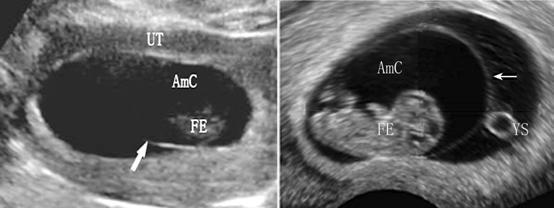

胚胎/胎儿在妈妈的子宫内生活在类似于水囊的结构内,在水中,胚胎/胎儿可以自由地活动,并受到全方位的保护。早期超声检查显示的妊娠囊并不是羊膜囊。尽管羊膜与胚胎及卵黄囊近同时发生,在第7孕周时可以经阴道超声检查显示,但因为其厚度仅有0.02mm~0.5mm并紧贴胎体而难以显示。第6孕周以后、顶骶径7 mm或以上时,随着胚胎屈曲和羊膜腔逐渐增大,羊膜在妊娠囊内胎体周围形成球形囊状结构,即羊膜囊;羊膜囊与其外侧的绒毛膜腔之间纤细的膜状回声即为羊膜。大多数情况下,只有与超声声束垂直的部分羊膜可能显示(图1)。由于羊膜囊增大迅速、羊膜菲薄,超声显像检查常不易显示。12孕周以后随着羊膜囊的扩大、羊水增多,羊膜与绒毛膜逐渐融合,绒毛膜腔消失。

图1 羊膜囊声像图(UT:子宫;AmC:羊膜腔;FE:胎芽;YS:卵黄囊;箭头所示为羊膜 )